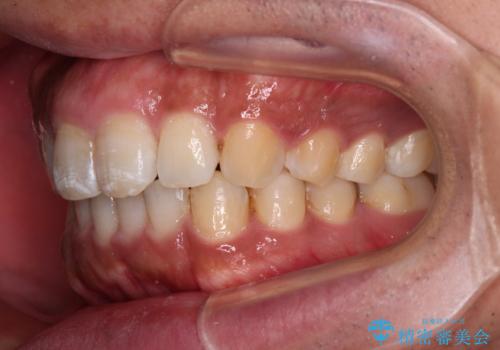

- 上下前歯部の叢生を気にして来院された患者様です。

レントゲン撮影により、右上奥歯が折れていることが分かりました。

患者様自身も何となく違和感を覚えていたとのことで、インプラント補綴治療を行うこととしました。

歯列不正は比較的軽微であったので、インビザラインによる矯正治療とし、矯正治療中にタイミングを見て抜歯とインプラント埋入を行う予定としました。